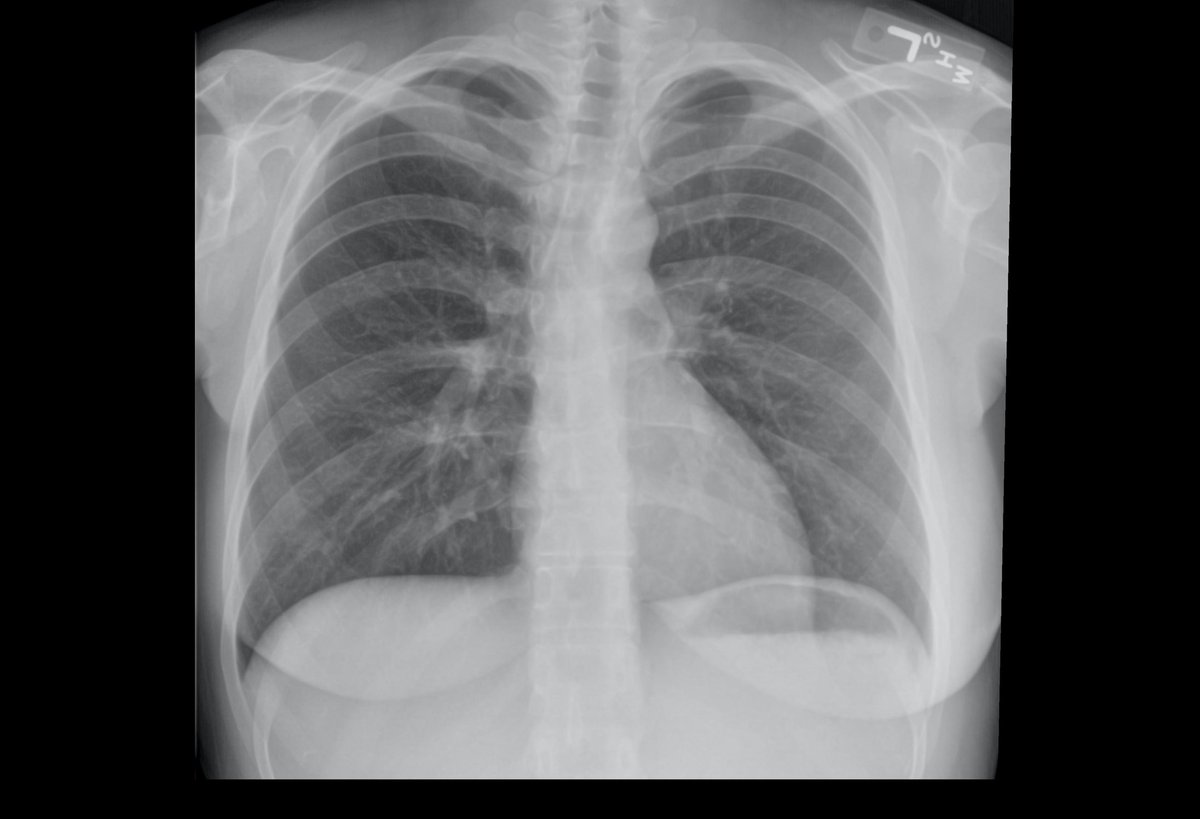

image of chest x-ray